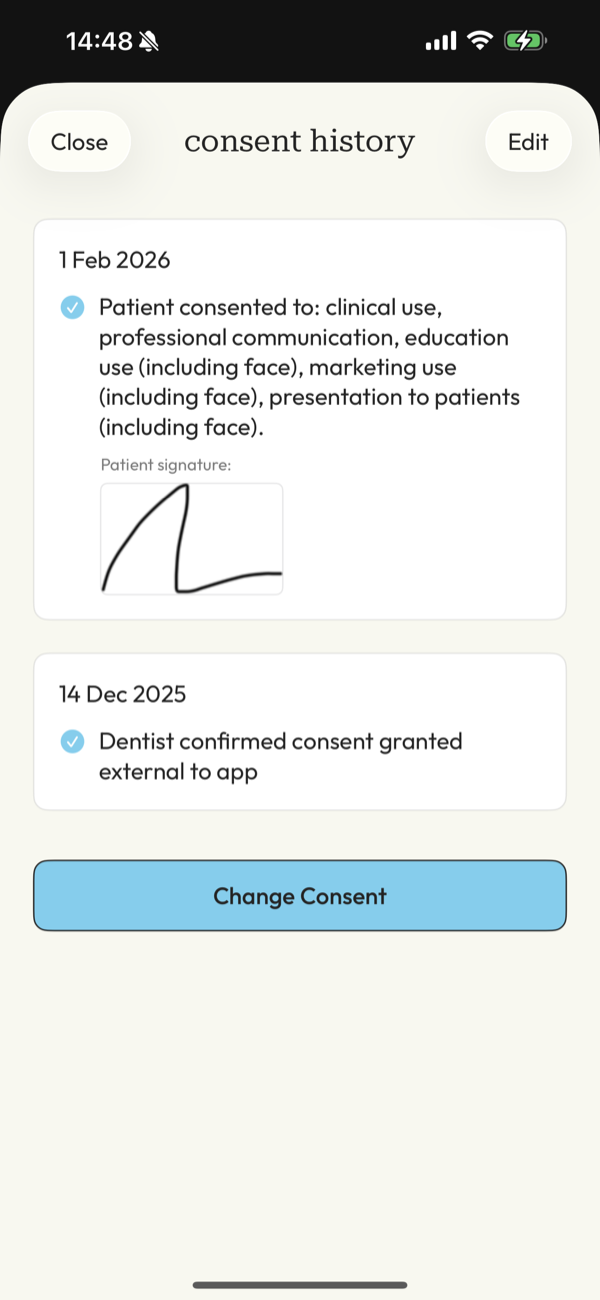

compliance worries

Managing patient consent for GDPR/HIPAA along with compliant storage and delivery can be a nightmare.

peace of mind

A system that puts clients at ease and you mind at rest, knowing you have the right consent and images are safe and secure.

What about consent and GDPR?

Handled as part of the workflow.

DentalFolio supports structured consent recording, allowing documentation of how images are intended to be used, such as for clinical records or education. A clear audit trail is maintained if needed.

Responsibility remains with the clinician. The app supports good practice but does not replace professional judgement.